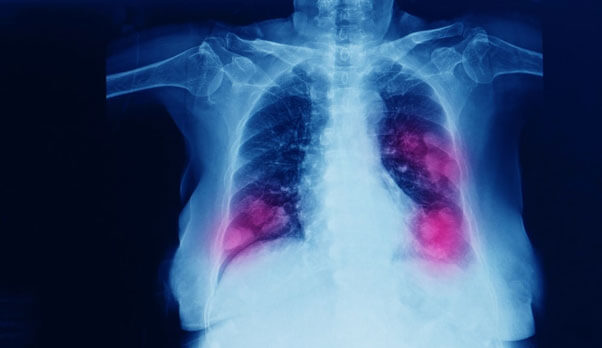

Lung Surgery

Lung surgery is performed to repair or remove lung tissue. It is done under general anaesthesia, and the two main approaches are thoracotomy (open chest surgery) and video-assisted thoracoscopic surgery (VATS), which is minimally invasive. These surgeries help treat infections, tumors, trauma, and other serious lung conditions.